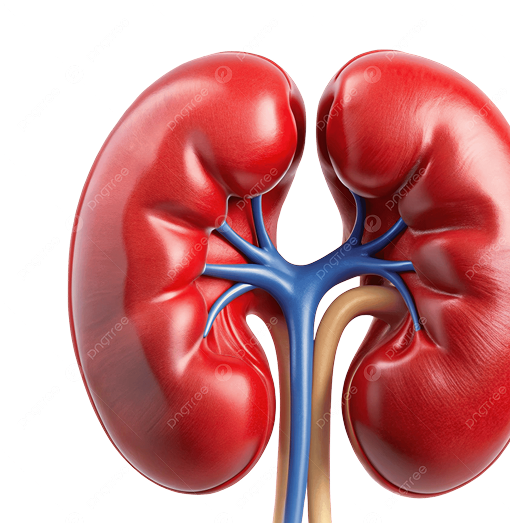

About kidneyCare

We, in KidneyCare specialize in managing logistics, supplies, and support services for nephrology care, ensuring efficient and affordable dialysis operations.We aim to transform dialysis services by providing a positive and reliable experience for every client, delivering exceptional value, and setting a high standard of professionalism in our logistics solutions. Out mission is continuously improve our services through comprehensive, integrated, and innovative solutions that are delivered quickly, efficiently, and safely.